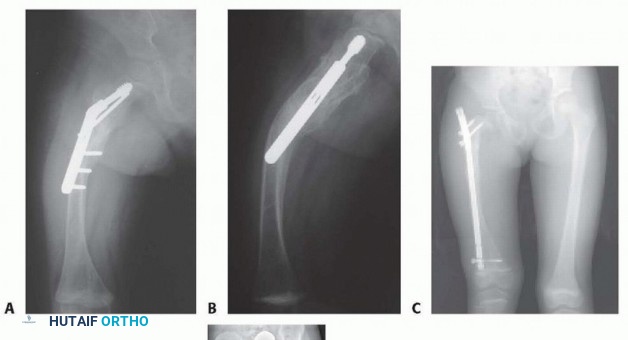

FIG 3 • A,B. Plating of the proximal femur in a young child with progressive bowing pain and recurrent fractures at the end of the plate. C. An 8-year-old child treated with an adult nail with lateral migration distally, coxa vara, and proximal growth inhibition. D. The same child treated with the Fassier-Duval nail and valgus osteotomy 6 months postoperatively. E. Follow-up near maturity demonstrating telescoping of the nail, maintenance of the valgus neck-shaft angle but residual leg length discrepancy related to initial surgery.

Plating predictably leads to stress reaction, progressive deformity, and fracture (FIG 3A,B). Use relatively small, flexible nails to share stress.

Excessively rigid nails may lead to disappearing bone (FIG 3C,D). Do not remove nails electively.

## TECH FIG 4 • A. A 2½ year-old boy with OI who developed progressive painful right coxa vara with walking.

B. Age 3 developing coxa vara on left with progression in right hip. C. Age 3 bilateral valgus osteotomies. Note valgus correction and alignment of lateral cortex of the proximal segment with right femoral shaft. D. Distal femoral osteotomy to correct associated diaphyseal varus. E. At 13-month follow-up, maintenance of correction is demonstrated. The femoral head is growing away from the wires, and varus may recur.